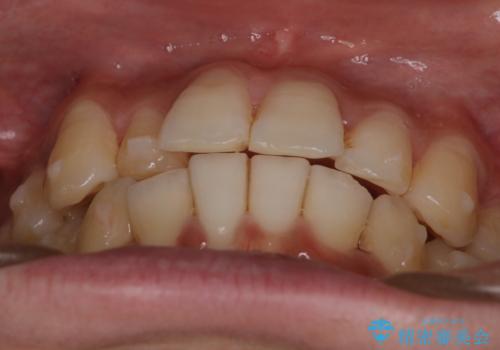

前歯のガタガタを治したい。

- 凸凹を治したいと来院された患者様です。

インビザラインにて、遠心移動を行いながら綺麗に配列することができました。

側切歯が低位の場合、反対咬合を改善した後に挺出させるのはワイヤーの方が適しています。